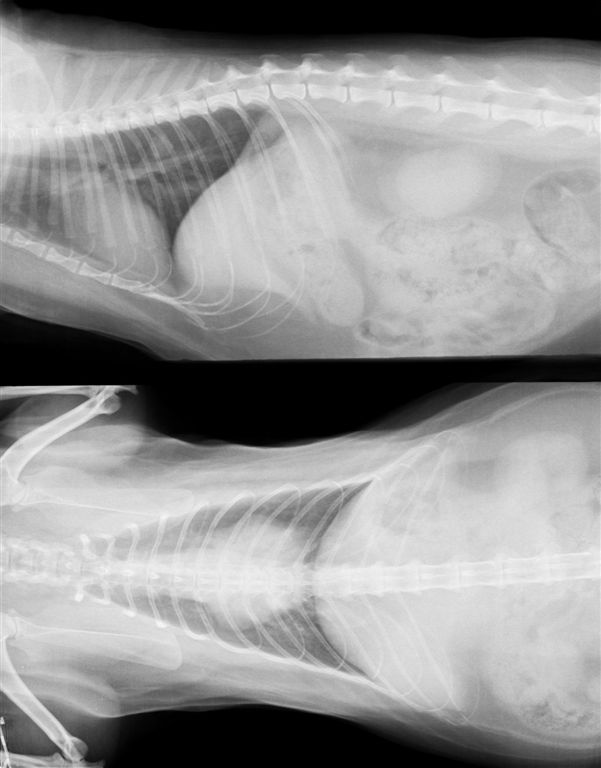

13歳 猫 メス

診断:乳腺腺癌

肺後葉に7mm大の転移像が見られる

手術後6ヶ月定期検査で発見された。猫の乳腺癌は1cm以下の段階でも遠隔転移を考慮に入れたほうがよい